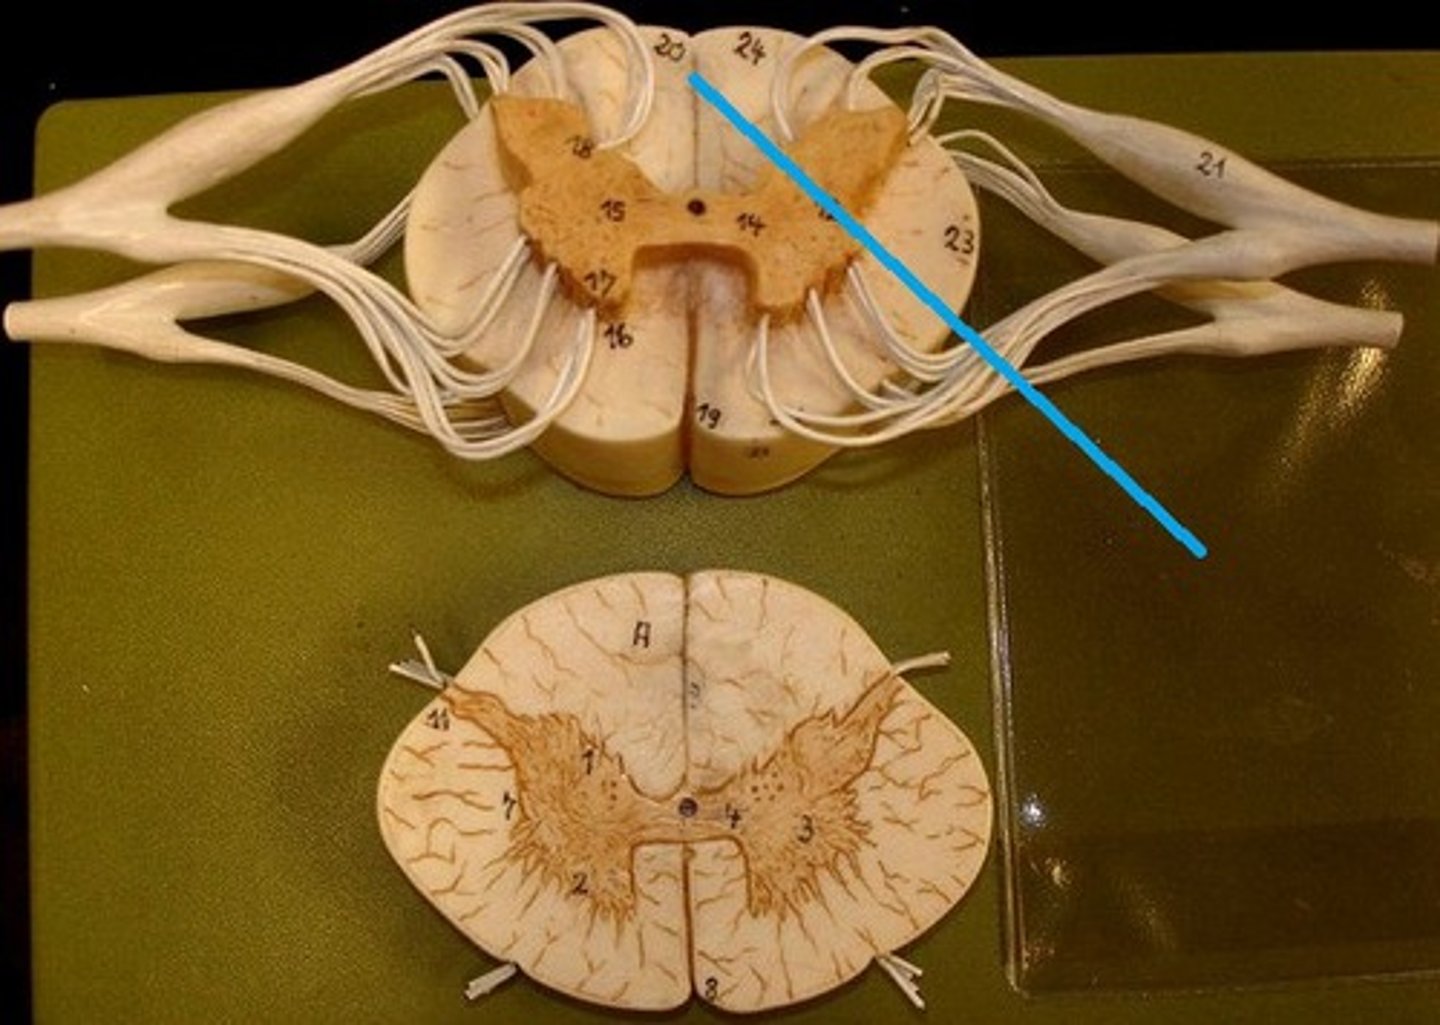

spinal cord

a major part of the central nervous system which conducts sensory and motor nerve impulses to and from the brain; housed within the vertebral canal

central canal of spinal cord

center of spinal cord which contains cerebrospinal fluid

posterior median sulcus

a shallow vertical groove dividing the spinal cord throughout its whole length in the midline posteriorly.

anterior median fissure

a groove along the anterior midline of the spinal cord that incompletely divides it into symmetrical halves

gray matter of the spinal cord

cell bodies, dendrites, and unmyelinated axons arranges in a butterfly shape with anterior and posterior "horns"

posterior (dorsal) horns

contain axons of sensory neurons and cell bodies (sensory nuclei) of interneurons

31 pairs of nerves arising from the spinal cord; letter abbreviation for region of spine they originate from; forms where the anterior and posterior roots join; mixed nerves (contain sensory and motor fibers)

posterior (dorsal) rootlets

merge to form a root

posterior (dorsal) root

contains sensory axons

posterior (dorsal) root ganglion

contains cell bodies of sensory neurons

true spinal nerve

anterior root

contains motor axons